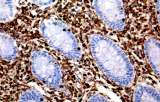

A imunohistoquímica (IHQ) com anticorpos primários CE/IVD é essencial para o diagnóstico e classificação precisos de malignidades ginecológicas e mamárias. Estes anticorpos permitem a deteção precisa de marcadores tumorais e proteínas celulares, apoiando o diagnóstico diferencial e guiando estratégias terapêuticas personalizadas.

Estudos recentes destacam o valor diagnóstico das proteínas do complexo SWI/SNF, particularmente ARID1B, na identificação de malignidades ginecológicas desdiferenciadas e indiferenciadas – tumores agressivos com mau prognóstico. A IHQ de ARID1B oferece elevada especificidade e está cada vez mais integrada em painéis diagnósticos para melhorar a precisão. Painéis com marcadores adicionais também apoiam a diferenciação de sarcomas uterinos, aumentando a exatidão diagnóstica. Evidência emergente sugere que ARID1B pode representar um alvo terapêutico potencial no carcinoma ovárico de células claras, embora as aplicações clínicas permaneçam em fase investigacional.